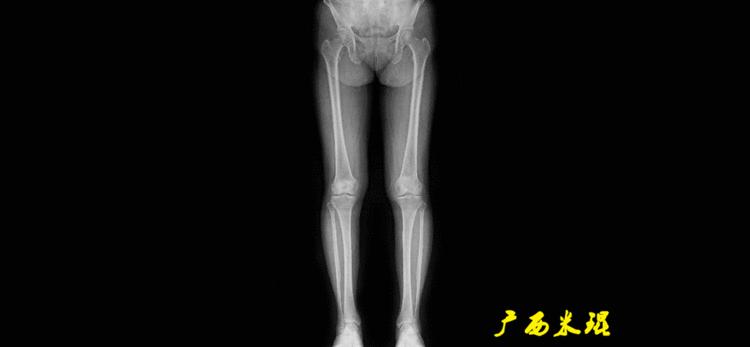

下肢力线及相关角度测量的前提是必须拍摄标准的站立位也就是负重位的下肢全长片。目前这样的照片都是放射科的技师在电脑上拼接出来的,大部分医院的DR都能够做到这一点。

患者直立于摄影架上,后背贴近摄影架,双手自然下垂,膝关节尽量伸直,足部与双肩同宽,要求投照时双髌骨朝正前方,通常患者双足尖应平行向前即可。

提醒一下大家,拍摄过程中应避免下肢的外旋和内旋。如果有一侧肢体短缩时,投照应当用脚垫垫高短缩肢体,使骨盆保持水平,这样下肢短缩测量才精确。如果有肢体旋转畸形时,还是以髌骨朝前为标准,虽然此时双足可能不能保持平行。

无论如何,拍摄出来的下肢全长片必须包含髋关节中心、膝关节中心及踝关节中心,否则对临床是无用的。有了一张下肢的全长照片,我们需要确定下肢关节的中心点,通过中心点画出下肢的各种轴线,然后利用轴线与关节线的相交得出各种所需要的角度。